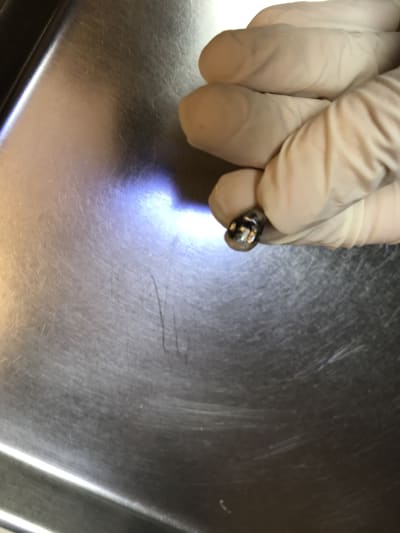

C’est ballot elle pouvait être recollée celle-là, on va la refaire en RAC0.